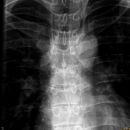

Foramen arcuale bzw Kimmerle Anomalie